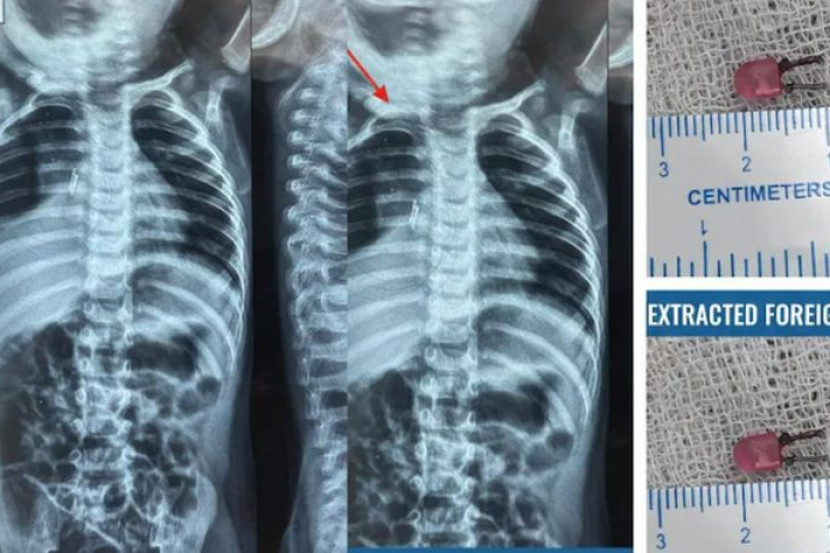

Doktor berjaya mengeluarkan sebiji mentol LED kecil yang tersangkut di saluran pernafasan kanak-kanak berkenaan. -Foto NDTV

SEORANG kanak-kanak lelaki berusia satu tahun yang disangka menghidap pneumonia gara-gara mengalami demam panas dan batuk kronik selama lebih sebulan, rupa-rupanya berdepan keadaan lebih serius apabila sebiji mentol LED (diod pemancar cahaya) kecil didapati tersangkut di dalam saluran pernafasannya.

Prosedur bronkoskopi dijalankan dan doktor berjaya mengeluarkan sebiji mentol LED sepanjang satu sentimeter yang tersangkut di saluran pernafasannya.